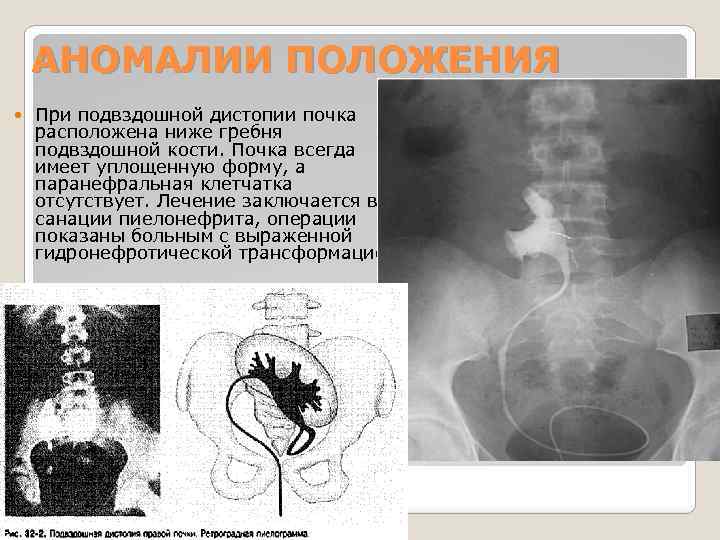

АНОМАЛИИ ПОЛОЖЕНИЯ При подвздошной дистопии почка расположена ниже гребня подвздошной кости. Почка всегда имеет уплощенную форму, а паранефральная клетчатка отсутствует. Лечение заключается в санации пиелонефрита, операции показаны больным с выраженной гидронефротической трансформацией.

АНОМАЛИИ ПОЛОЖЕНИЯ При подвздошной дистопии почка расположена ниже гребня подвздошной кости. Почка всегда имеет уплощенную форму, а паранефральная клетчатка отсутствует. Лечение заключается в санации пиелонефрита, операции показаны больным с выраженной гидронефротической трансформацией.